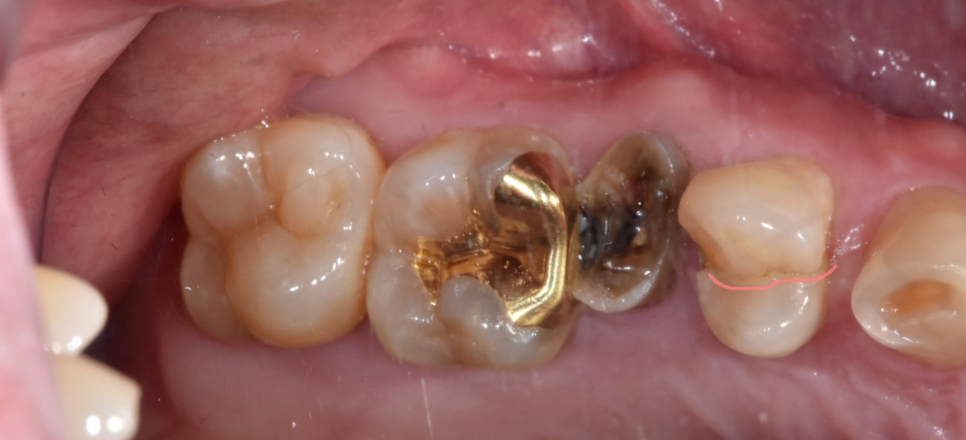

250529 강한 힘이 가해져 쪼개져버린 치아

특히나 신경치료를 받은 치아는

수분 함량이 줄고 건조해지기 때문에 쉽게 깨지는 특성이 있습니다.

크라운으로 덮어 보호해주지만

더욱 조심해주셔야해요.

230403 신경치료 후 크라운을 덮어 보호한 경우